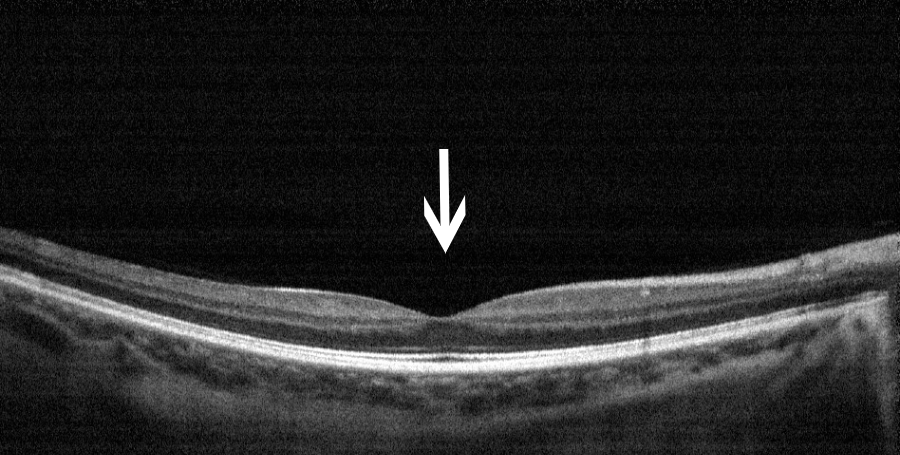

正常后极部眼底彩照及黄斑区OCT图

眼底彩照:眼底后极部各个组织结构

OCT:黄斑区视网膜的断面图,凹陷处为黄斑中心凹